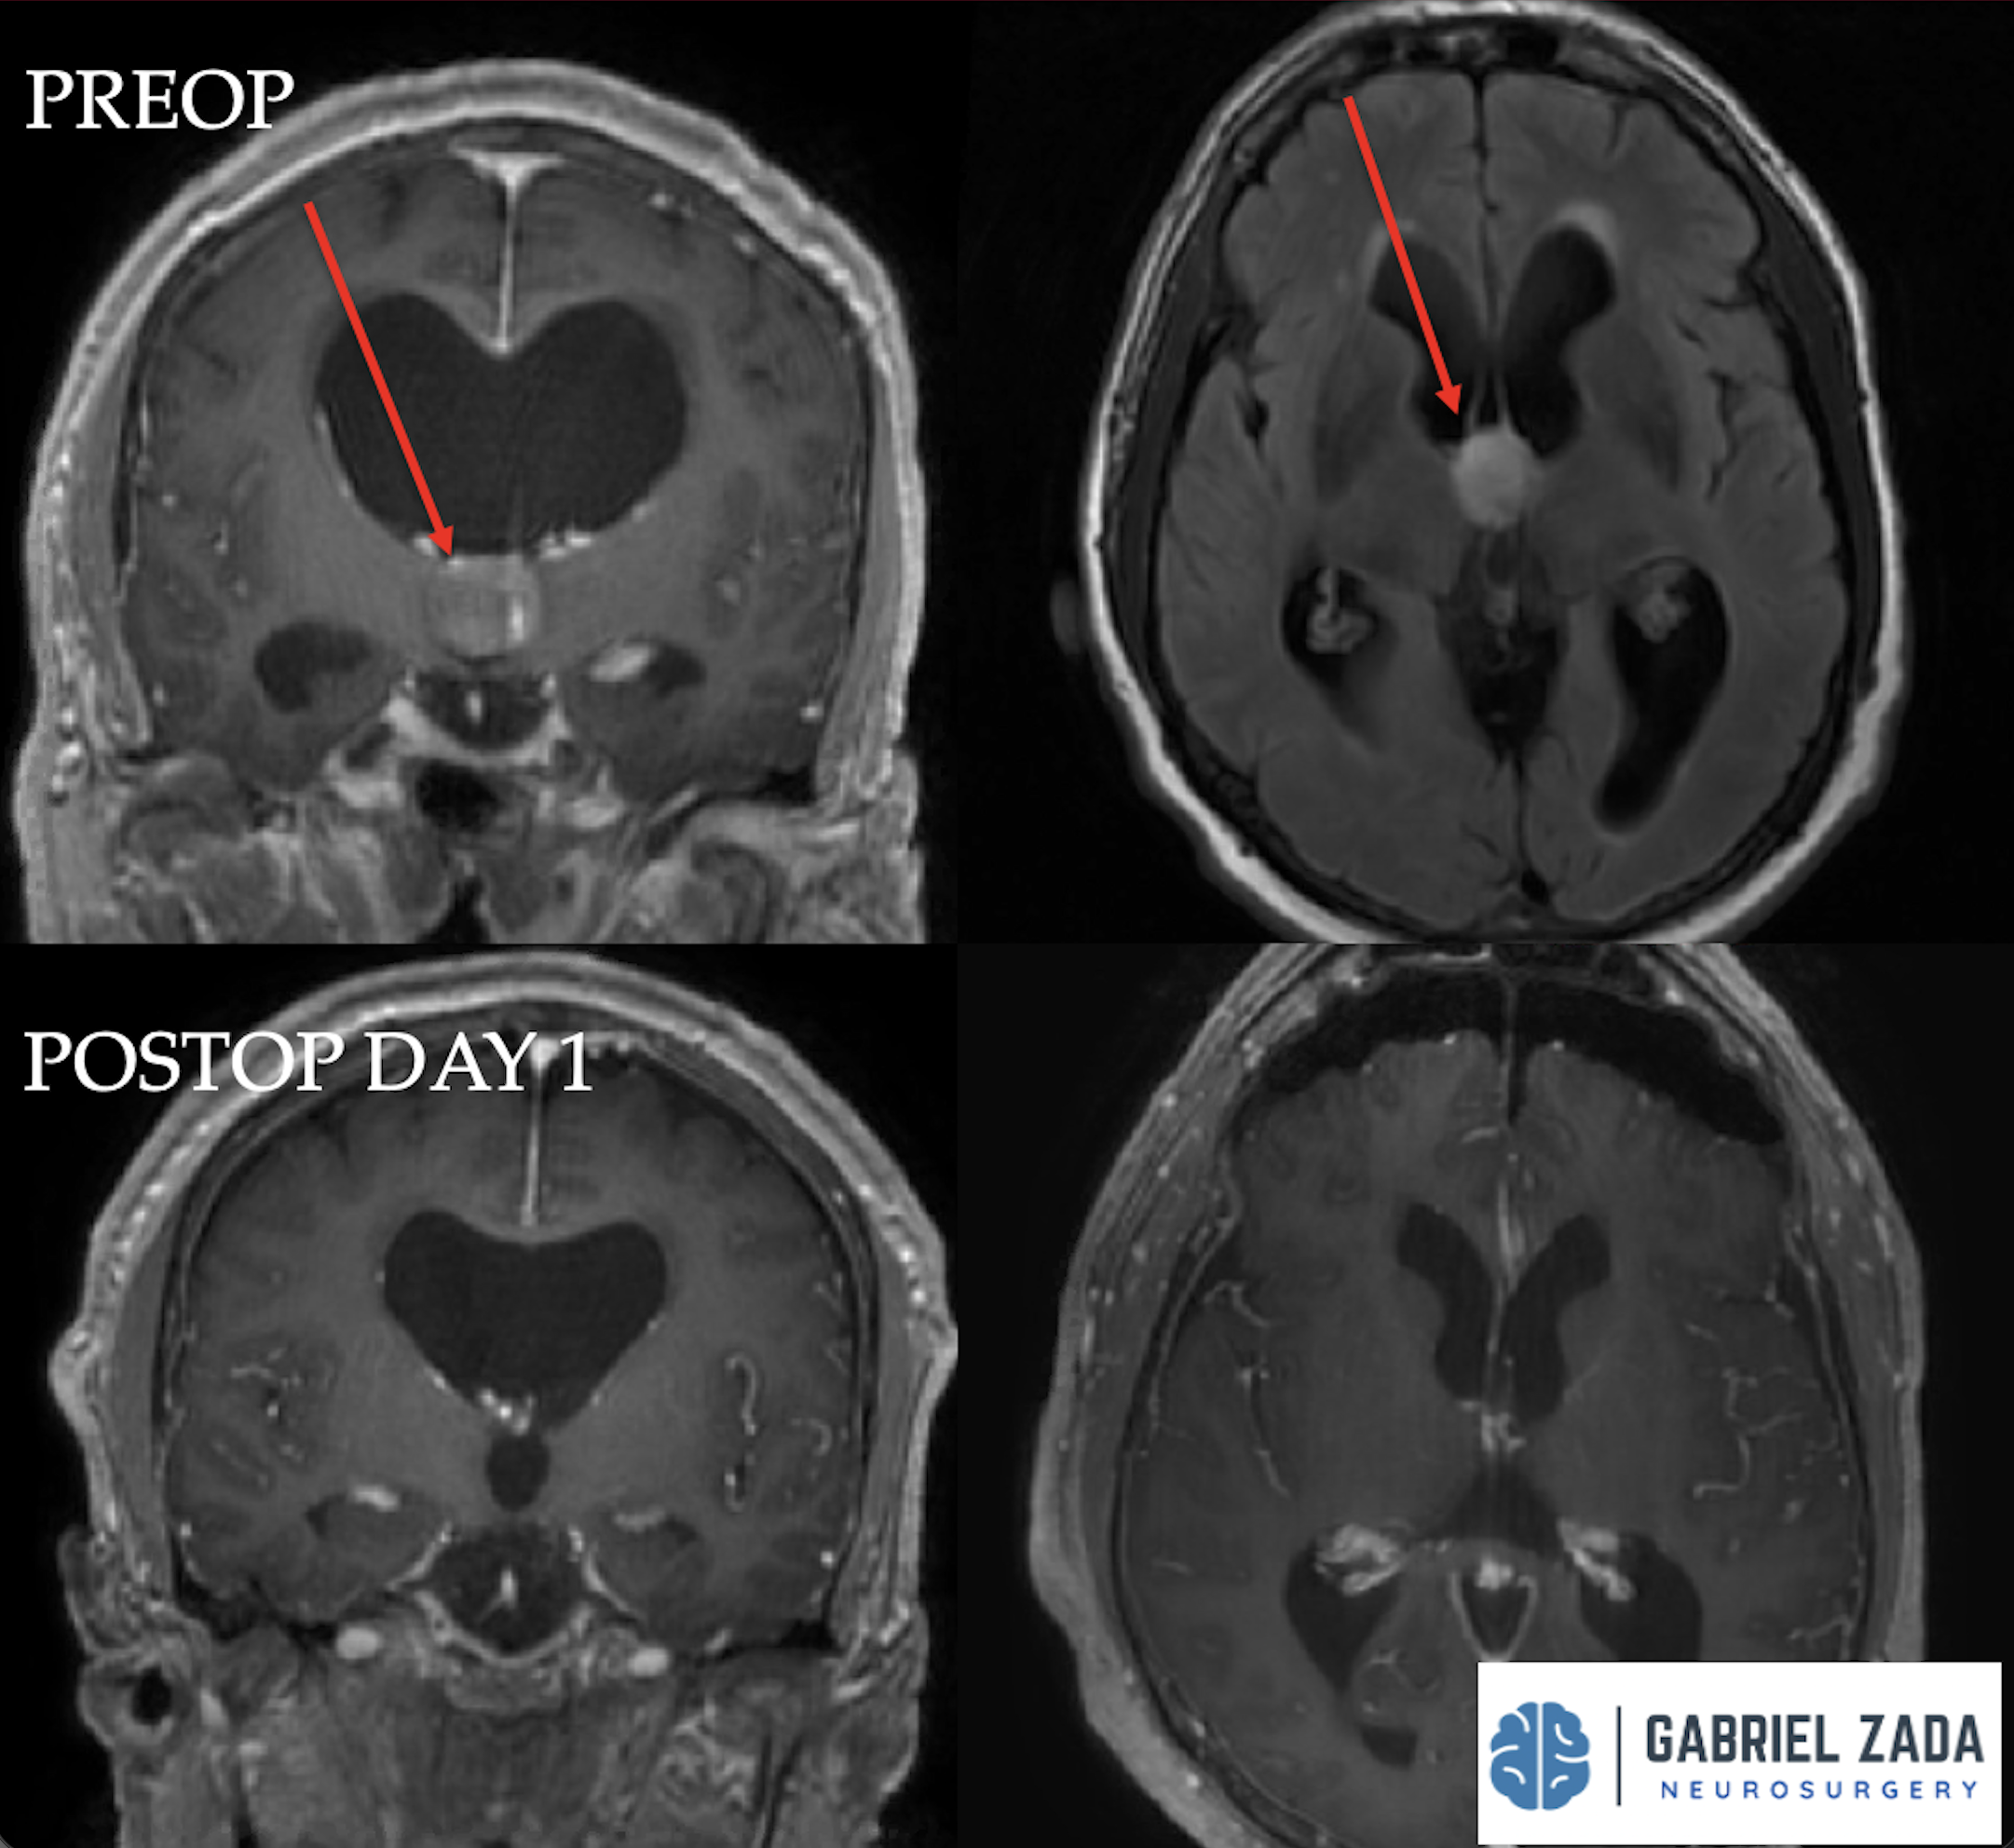

Explore this comprehensive gallery featuring pre‑ and post‑operative imaging of patients with skull‑base tumors treated by Gabriel Zada, MD, MS, FAANS, FACS. These cases highlight Dr. Zada’s expertise in advanced neurosurgical techniques and outcomes.

*Representative cases shown for educational purposes. All images de-identified. Individual results vary.